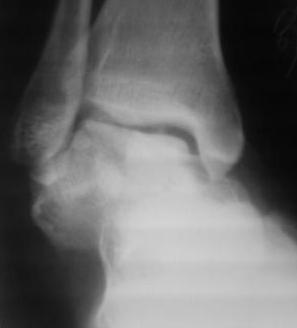

Осколчатый перелом таранной кости

Поступил б-ной, 1965г.р., вчера упал с высоты. В травм. пункте произведена репозиция. наложена гипсовая повязка.

Обратился с сильными болями в стопе, срочно рассечена гипсовая повязка, выраженный отек стопы, сплошные фликтены, конечность уложена на шину Белера, скелетное вытяжение за пяточной кость, антибиотики, анальгетики, клексан, трентал.

1.Сразу готовится к артродезу?

2.Или постараться открыто собрать осколков?(тогда вероятность асеп.некроза большая)

3.Дистракцион.остеосинтез А.В.Ф.,и дальше время покажет?